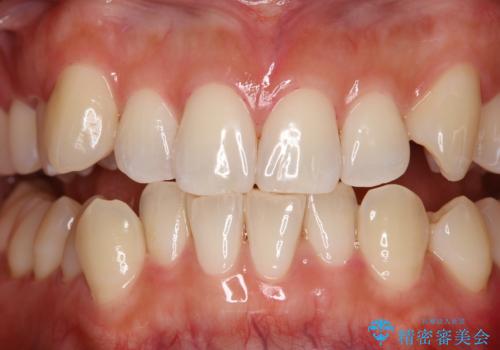

染め出しをしてエアフローで綺麗にクリーニング

染め出しを行い、歯みがき指導とエアフロー60分コースを行いました。

従来の荒い研磨剤などを用いた歯面への負担が大きいクリーニングとは異なり、歯質の負担を最小限にした歯面清掃と歯周ポケット内のメンテナンスを行えます。